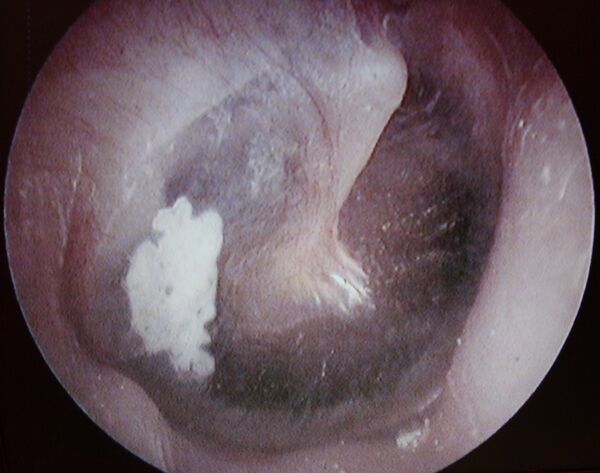

Мирингопластика

Мирингопластика (новолат. myringoplasty) — операция по восстановлению целостности барабанной перепонки.[2]

Метод мирингопластики, позволяющий достичь необходимой герметичности и избежать последующих дегенеративных изменений в трансплантате. Для устранения перфорации, из фасции височной мышцы формируют двойной фасциальный лоскут, размещают его с двух сторон барабанной перепонки.[3]